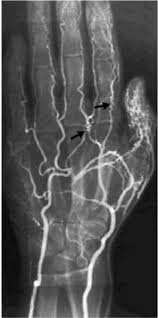

Artografia

Definición

La artrografía consiste en la obtención de imágenes radiológicas de la articulación que se desee estudiar mediante el empleo de una fuente emisora de radiación ionizante (rayos X), una fluoroscopia o fuente emisora de radiación ionizante continua, un medio de contrate yodado, un monitor y un ordenador.

A diferencia de la radiografía simple articular que utiliza una fuente emisora de radiación ionizante única mediante la cual se obtienen imágenes radiológicas estáticas de la articulación estudiada; la artrografía, emplea además una fluoroscopia o fuente de radiación ionizante continua, que permite obtener imágenes dinámicas o en movimiento de la articulación estudiada.